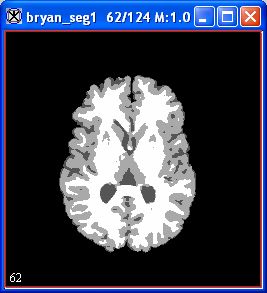

In a few moments, processing completes, and an image appears (Figure 4A).

Figure 4. FANTASM image